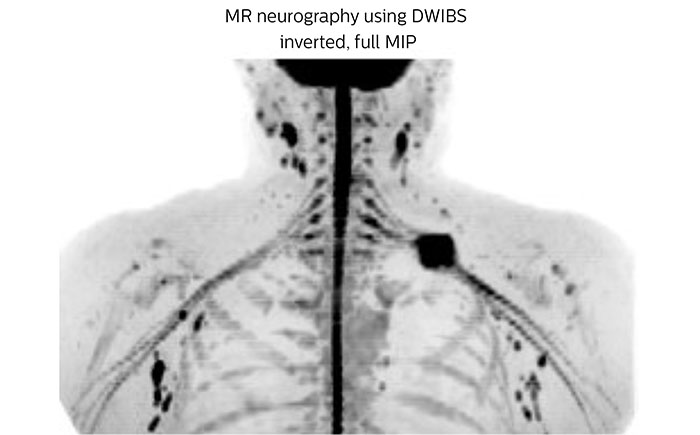

A 61-year-old female with a malignant lymphoma underwent an MRI exam with whole body diffusion weighted imaging (DWIBS) as well as PET. On the images shown, the resolution of DWIBS is better than PET, which allows visualization of the small pelvic lesions and almost no distortion is seen in the neck area.